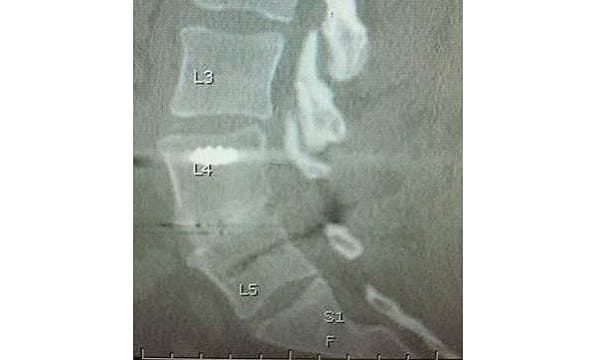

During NASS, Timothy Bassett, MD, of SouthEastern Spine Specialists, Tuscaloosa, AL, presented his ‘Early Clinical Experience with a PEEK-OPTIMA HA Enhanced Device for Lumbar Fusion’. The 1-2 level TLIF (Transforaminal Lumbar Interbody Fusion) procedure utilised the EVOS HA Device, from Cutting Edge Spine, intended for use in skeletally mature patients with Degenerative Disc Disease (DDD) of the lumbar spine, plus autograft bone with posterior instrumentation. No biologics were used in this series of nine patients.

The clinical results were evaluated for pain on the Visual Analogue Scale (VAS), opiate usage, neurological function, re-operations and complications. Fusion results were evaluated using anteroposterior (AP) and lateral X-rays at six weeks and 12 weeks, and a CT scan at six months. Dr Bassett concluded, “Very rapid visible bone fusion occurred in the interbody region in six weeks, according to plain radiographs, with correspondingly good clinical results including no neurologic consequences beyond 6 weeks, no implant migrations, no subsidence, and no pseudoarthroses. More importantly, 9/10 fusions were definitively solid on 6 month CT scan with autograft bone, despite some challenging patients. The one that didn’t show complete fusion was progressing to fusion and used one pack of tobacco daily, both pre- and post-operative, contributing to the fusion challenge.